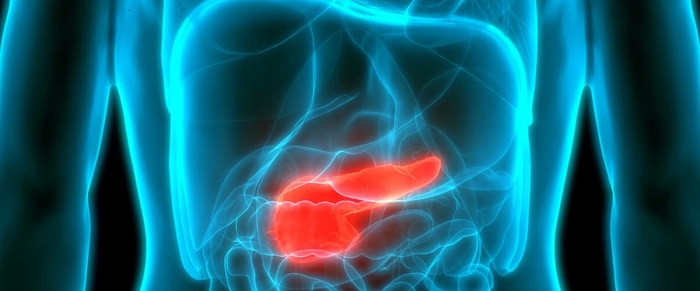

Nghiên cứu mới cho thấy nồng độ insulin trong máu cao liên quan đến ung thư tuyến tụy (07/12/2023)

Một nghiên cứu mới đã tìm thấy mối liên hệ giữa nồng độ insulin trong máu cao, thường thấy ở những người mắc bệnh béo phì và tiểu đường loại 2, với ung thư tuyến tụy. Các nhà nghiên cứu cho biết phát hiện của họ có thể dẫn đến các chiến lược phòng chống ung thư mới và nhắm mục tiêu điều trị để làm chậm hoặc ngăn chặn sự tiến triển của ung thư.